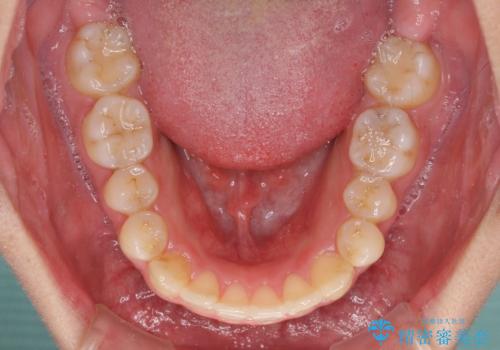

狭い歯列と前歯のデコボコ インビザラインによる矯正治療

- 上下前歯のデコボコを気にして来院された患者様です。

インビザラインによる上下歯列の拡大と、IPR(歯と歯の間を削る)にるスペースの獲得により、前歯のデコボコと狭い歯列を改善することとしました。

比較的軽度な歯列不正であったため、治療期間はそれほど長くはならないと予想されました。

しかしながら、あまりしっかりとマウスピースを装着していなかったため、思いの外期間が長引いてしまいました。

また、仕上がりの歯列にも若干の叢生が残ってしまいました。